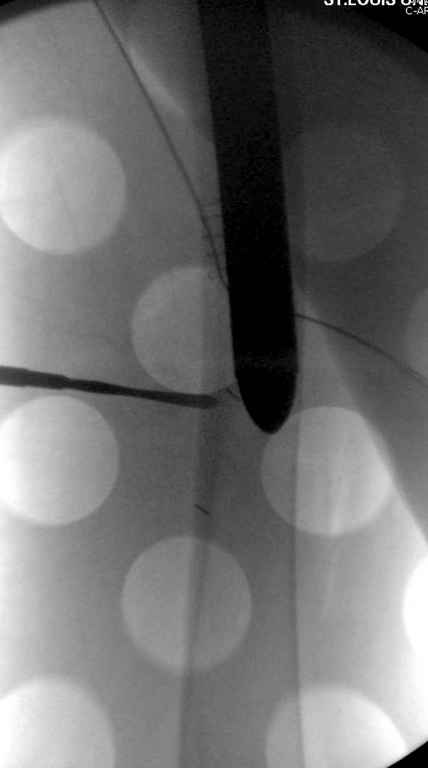

Вашему вниманию представляется похожий случай, пациентке 70, осложнился в течение одного месяца после операции. Ревизия с заменой сустава, кабельная фиксация на трохантер. При установке в дистальном диафизе обнаружен тонкий кортикальный слой и сделана профилактика от возможного перелома аллографтом.